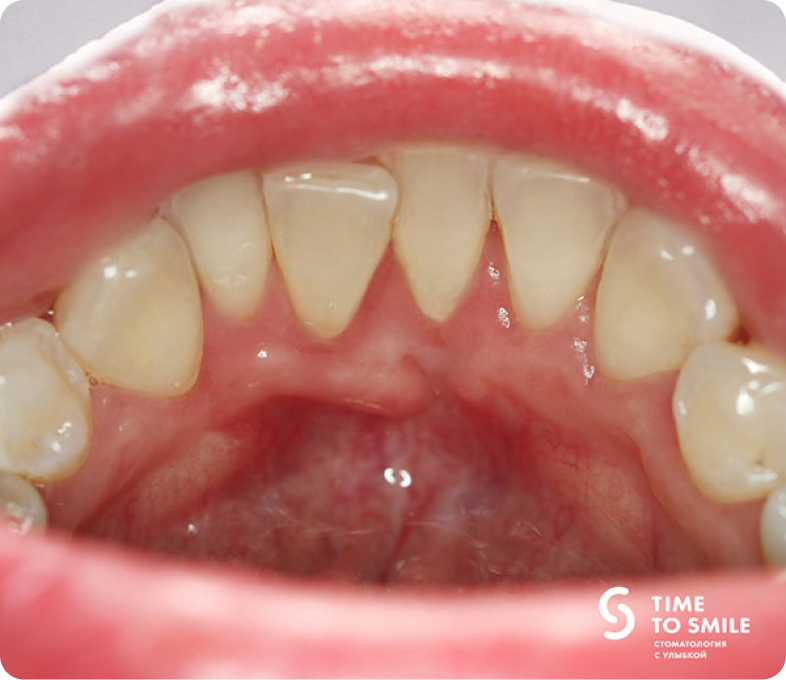

Рецессия десны – состояние, при котором происходит истончение и убыль мягких тканей, окружающих зубы.Причиной могут быть воспалительные процессы, механическая травма, неудовлетворительная гигиена полости рта, вредные привычки. В данном клиническом примере причиной рецессии десны в области нижнего резца с язычной стороны явилась хроническая механическая травма пирсингом.

Пациент в течение нескольких лет пользовалась украшением в области языка.

Механическое воздействие такого украшения привело к истончению, а затем к утрате десны в области нижнего зуба и оголению его корня.

Дефект десны приводит к хроническому воспалительному процессу, так как сложности гигиены в этой области ведут к накоплению зубного налёта.Пациент в течение нескольких лет пользовалась украшением в области языка.